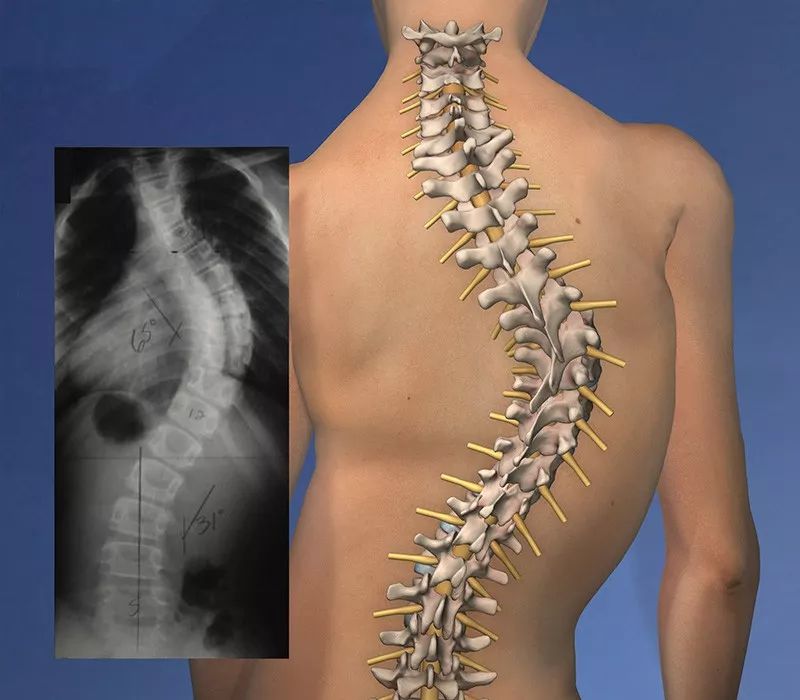

脊椎侧弯是一种常见的骨骼问题,在站姿下,不管从正面或背面看,正常的脊椎排列应该是身体左右两边对称,并且正常的脊椎排列从上到下是呈一直线的。

如果在站姿下看到脊椎向身体的任何一边弯曲歪斜,就是有可能是脊椎侧弯,左右手臂与躯干之间的空隙不对称,右侧肩膀较高。然而大部分的脊椎侧弯并不只有单一平面的左右倾斜,通常会伴随着脊椎旋转,往往也会影响到肩胛骨的动作,导致肩关节的活动度受限。

首先你需要确定你的脊柱侧弯程度到底有多严重,根据不同的严重程度有不同的矫正方法。

●严重

如果侧弯超过了40°,这就是属于严重的脊柱侧弯,就要考虑是否要进行矫正手术了。

●中度

20~40°的侧弯,属于中度的脊柱侧弯,我们可以通过一些康复训练进行治疗,同时需要使用支具进行治疗。

●轻度

对于不超过20°的侧弯,这就属于轻度,所以我们不必佩戴矫正器,单纯通过康复训练,就能有一定的康复效果。大部分人应该都是属于轻度的,所以着重以下面的方式进行康复。